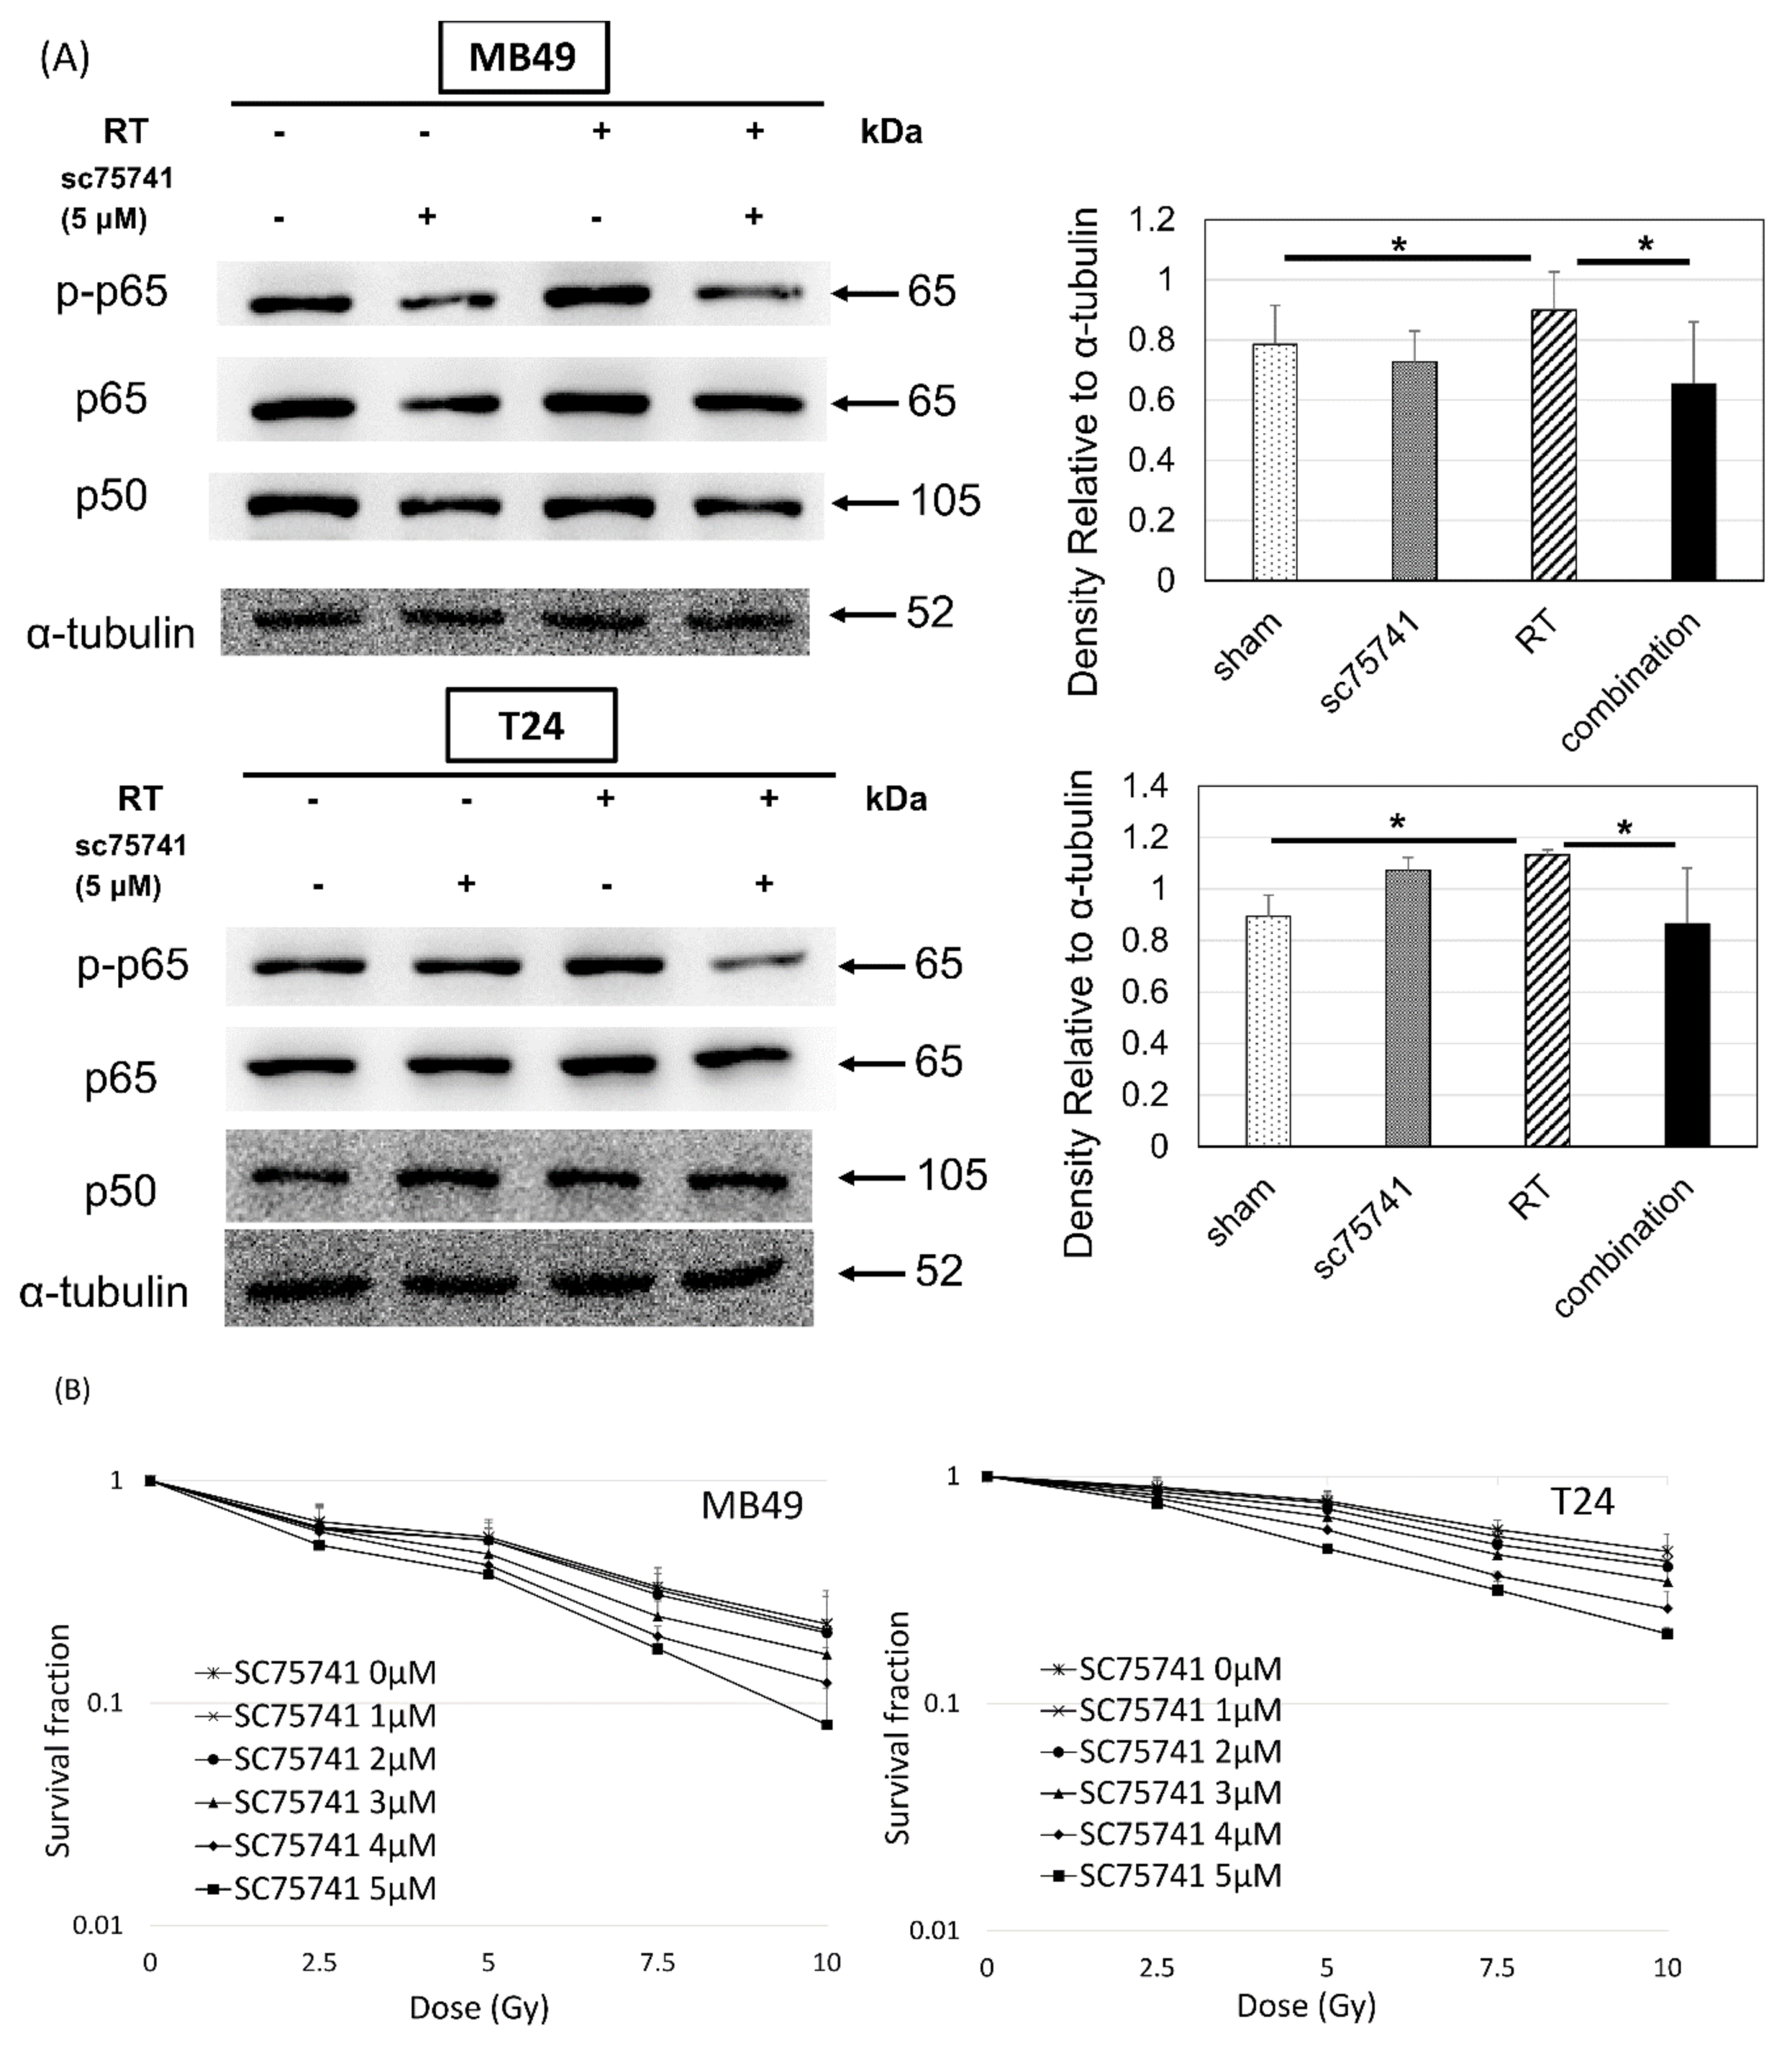

3.4. In Vitro Investigation of NFκB Expression of Irradiated Bladder Cancer Cells